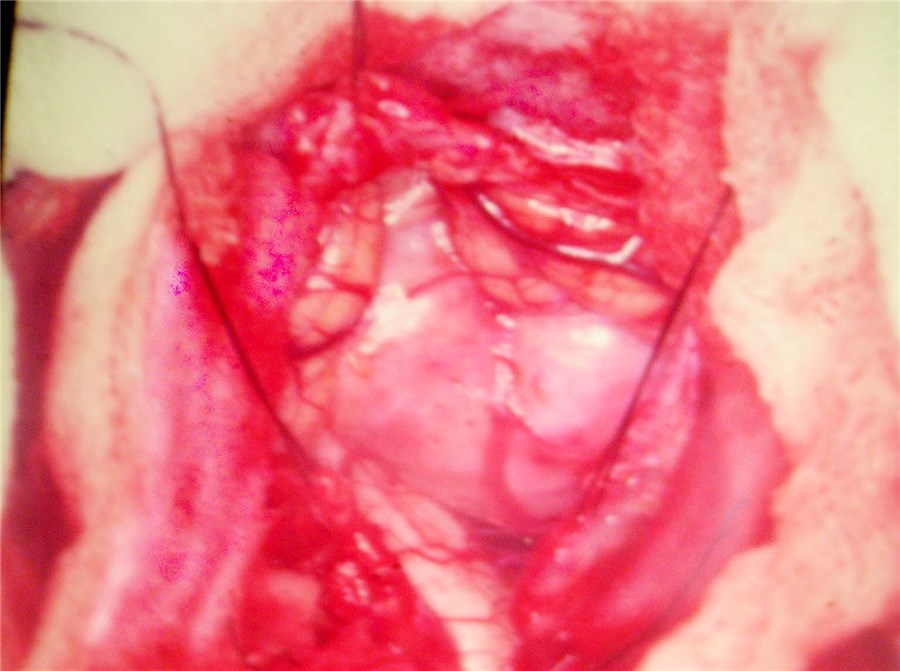

Arteriovenous malformations

Arteriovenous malformations of the brain are abnormal bunch of blood vessels that can rupture causing bleeding, or may cause seizures. Brain imaging (CT, MRI) is required for early diagnosis, while definitive treatment is carried out after cerebral angiography. Treatment implies craniotomy and excision of the AVM, which can be done safely in majority of the cases. Embolisation and radiosurgery are acceptable substitutes, but carry risk of further bleeding.